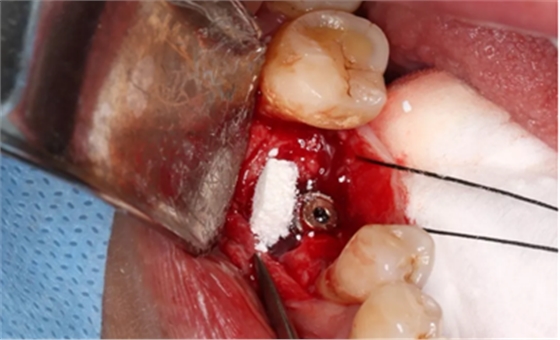

14、植骨手术过程

刮除肉芽组织及种植体表面清洁后,种植体唇侧骨缺损区植入人工骨粉。

(摄于2017年8月10日)

引导骨再生

无张力间断缝合切口。